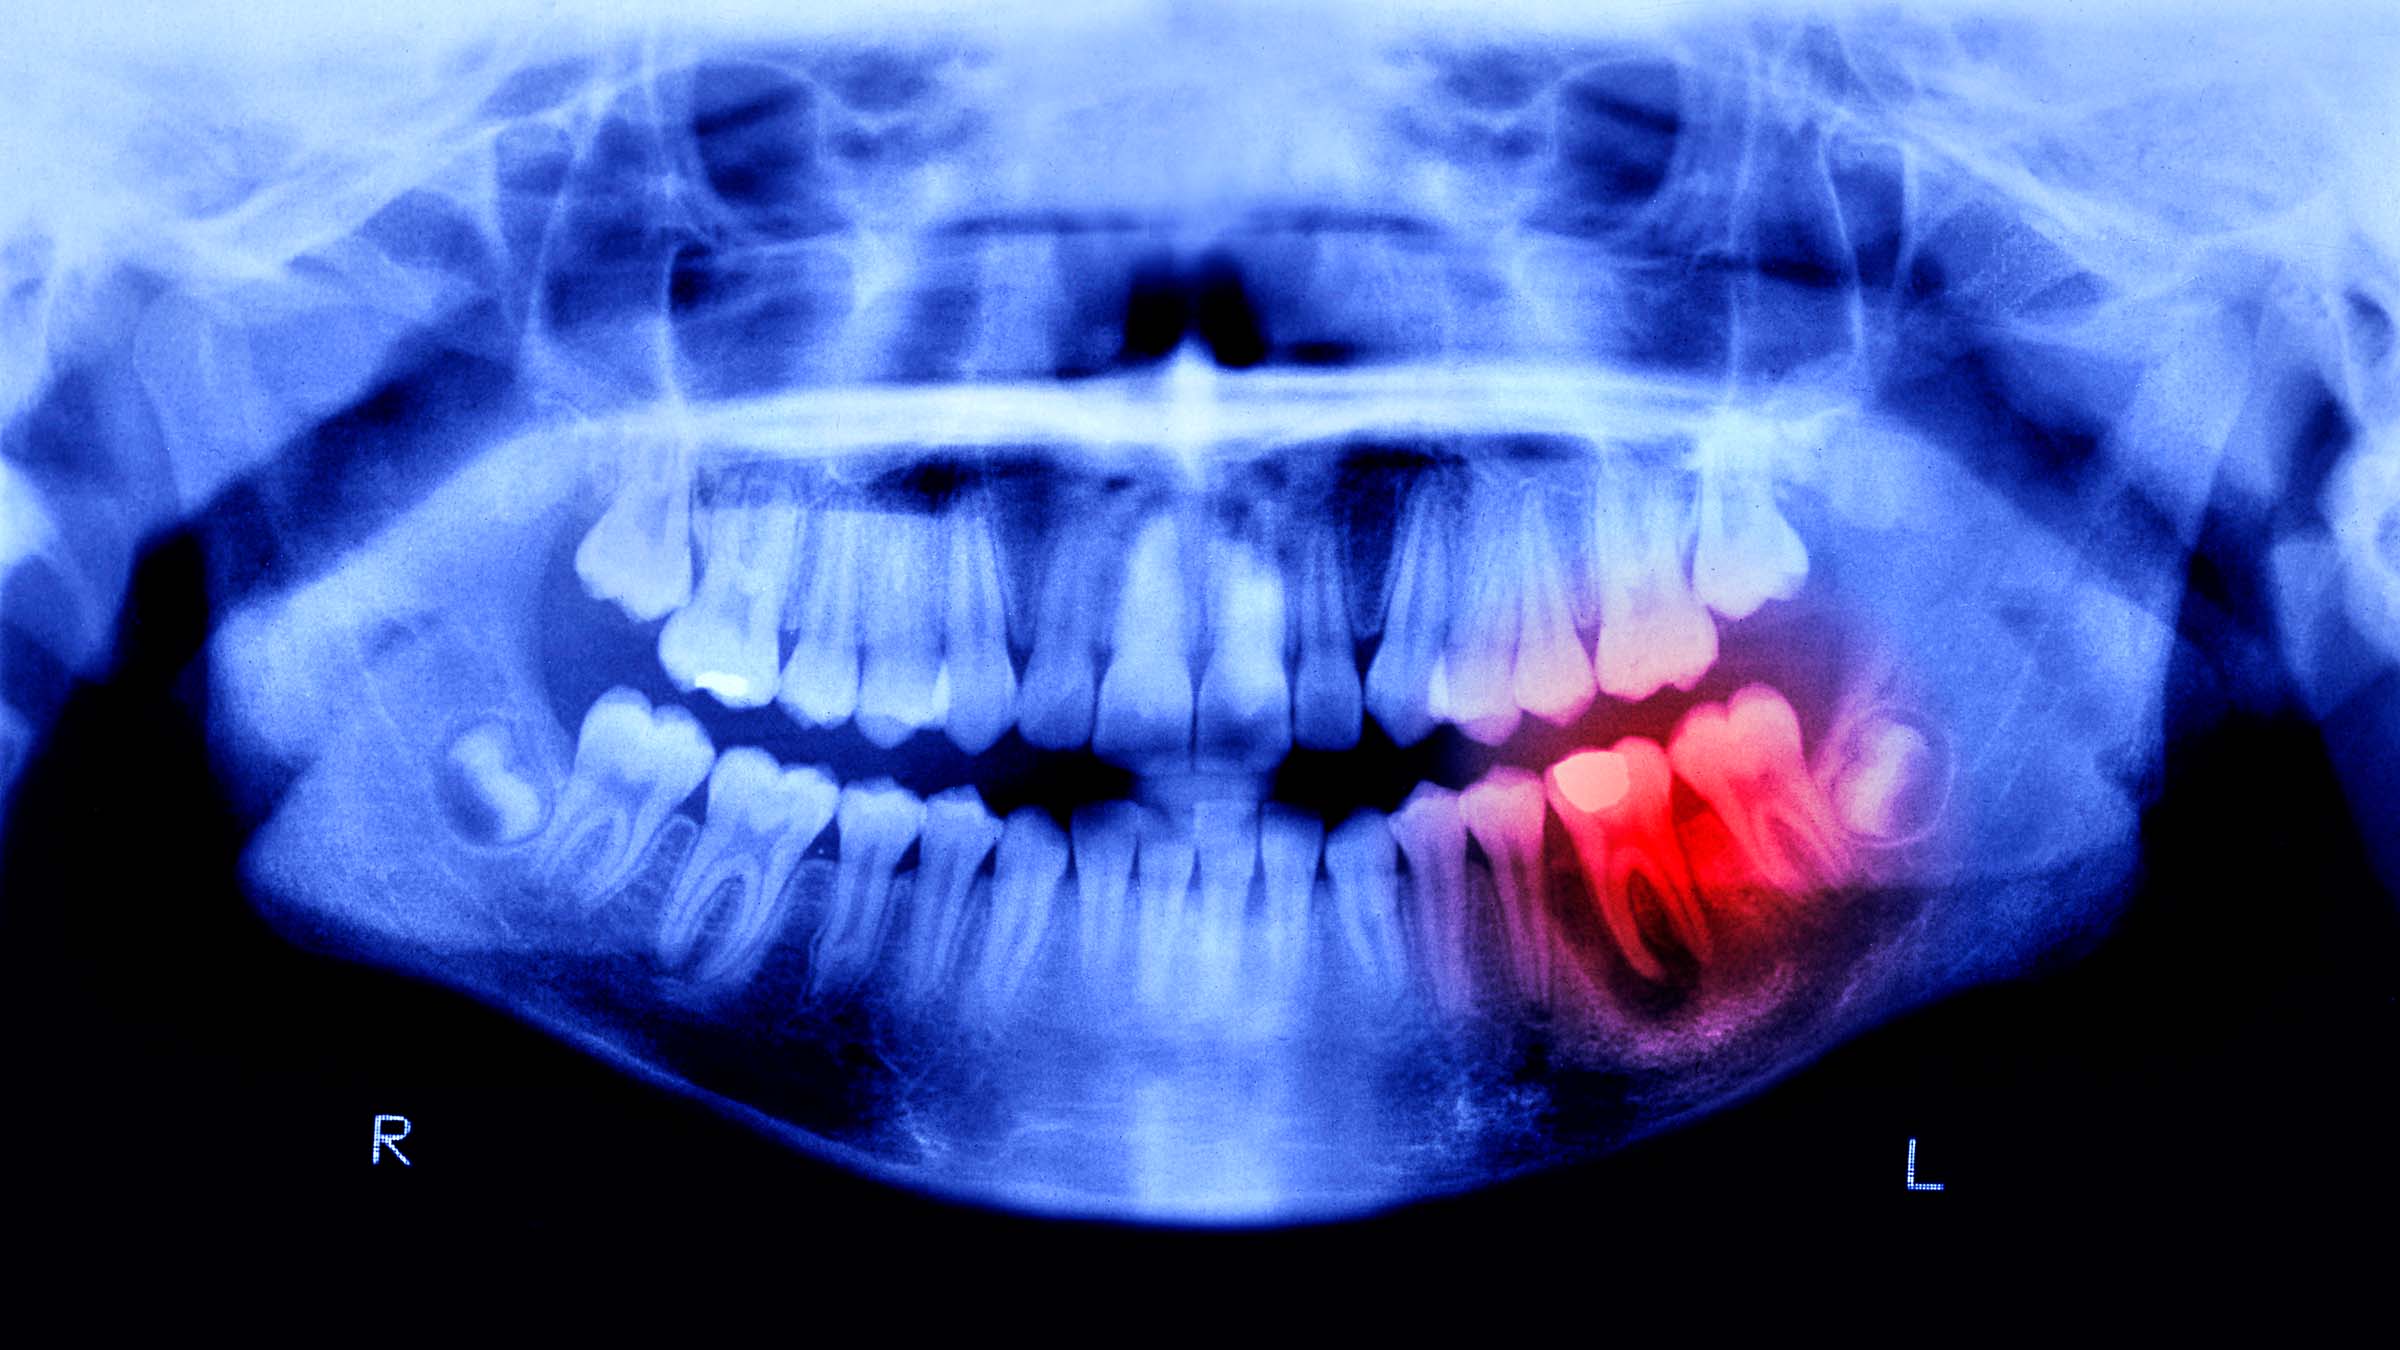

Fractures can be small chips in a tooth’s outer enamel layer, or to a larger extent, they can be full tooth breaks that expose the pulp – the nerves and blood vessels at the core of a tooth. There’s no life-threatening emergency here, but it’s certainly painful. The temporary filling material or glue in some dental emergency kits can protect the tooth and temporarily reduce pain until help is available. Fractures with exposed pulp may require more thorough repair, like a root canal.

(Photo: Peter Dazeley / The Image Bank via Getty)